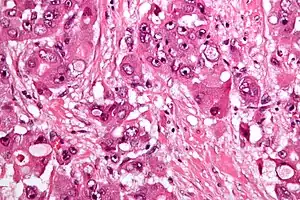

| Micrograph of fibrolamellar hepatocarcinoma showing the characteristic laminated fibrosis between the tumor cells with a low NC ratio. H&E stain. | |

The histopathology of FHCC is characterized by laminated fibrous layers, interspersed between the tumor cells. Cytologically, the tumor cells have a low nuclear to cytoplasmic ratio with abundant eosinophilic cytoplasm. Tumors are non-encapsulated, but well circumscribed, when compared to conventional HCC (which typically has an invasive border).